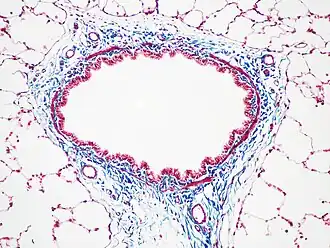

Бронх крысы, окраска трихромом Массона